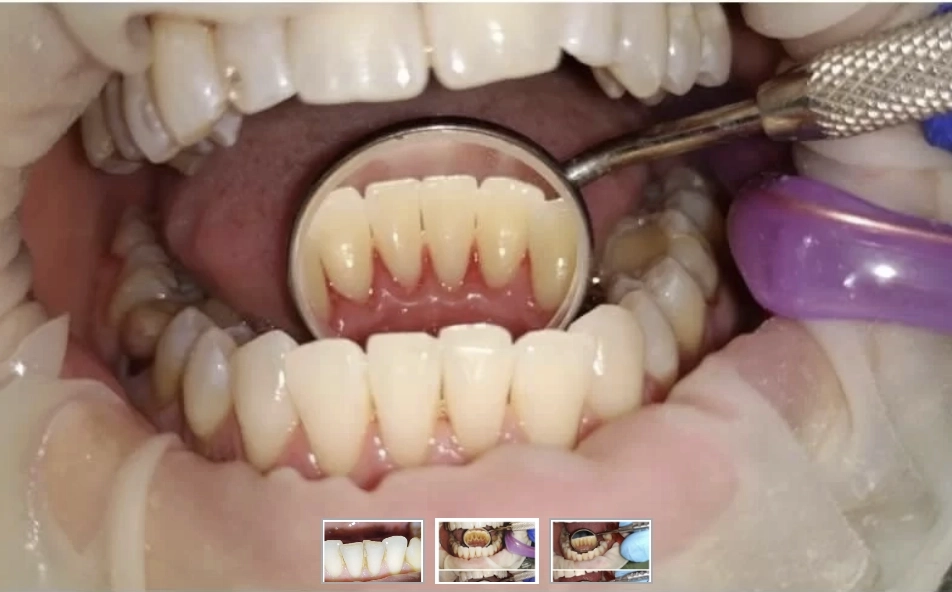

Dantų akmenų šalinimas (profesionali burnos higiena su air flow) – tai svarbiausia profilaktinė procedūra, leidžianti išvengti karieso, dantenų uždegimo ir periodonto ligų. Mūsų klinikoje naudojama moderni įranga užtikrina maksimalų komfortą ir nepriekaištingą švarą net sunkiai pasiekiamose vietose.